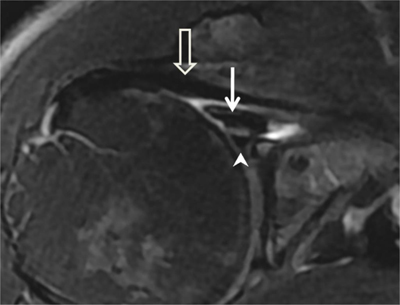

Figure 23

Inferior glenohumeral ligament. (A) Sagittal oblique PD-weighted MRA depicts the inferior glenohumeral ligament (thick arrows, A) with a high labral attachment (arrowhead, A). Coracohumeral ligament (thin arrow, A). (B) Sagittal oblique PD-weighted MRA shows the anterior band of the inferior glenohumeral ligament (white arrows, B) and the posterior band of this ligament (black arrows, B).